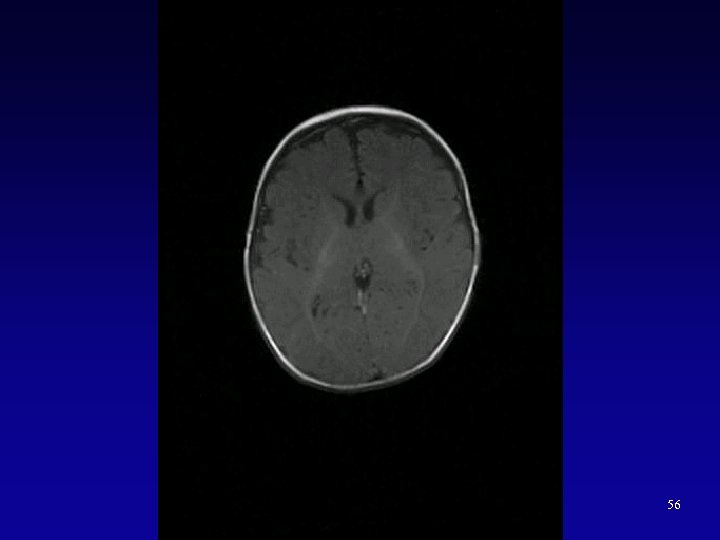

55

56